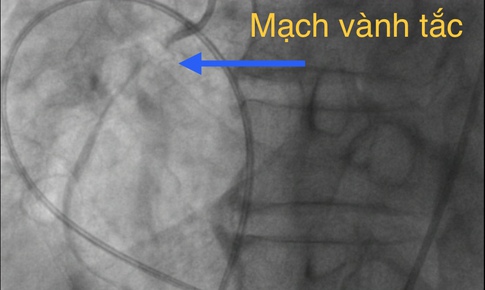

Khánh Hòa liên tục can thiệp thành công tim bẩm sinh cho trẻ em

Nhịp cầu Nhân ái - 29/07/2025 10:24SKĐS - Nhiều gia đình ở Khánh Hòa và khu vực lân cận có con mắc bệnh tim bẩm sinh đã được các y bác sĩ can thiệp kịp thời và thành công.